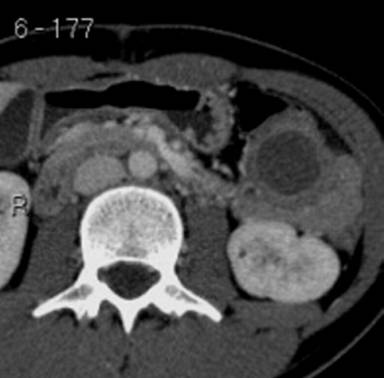

A 25-year-old woman was admitted to the hospital because of a three months persistence of abdominal discomfort localized in the upper left quadrant without any relationship with the food ingestion. The abdominal discomfort appeared immediately after an enucleoresection for a solid-cystic papillary tumor localized in the pancreatic tail; this tumor was found incidentally at an ultrasonographic examination carried out for dyspeptic symptoms. Surgery was carried out in a hospital outside Italy. She denied a history of alcohol consumption; she was no smoker and was no drug addict. On admission, the patient had painful at the deep palpation of the abdominal left upper quadrant without signs of peritoneal irritation. The arterial pressure was 115/70 mmHg and the cardiac rate was 72 beats per minute. Electrocardiography was normal and laboratory investigations were unremarkable. An abdominal computer tomography was performed (Image 1) and this examination showed a cystic lesion of 4.5x3.5 cm in size localized near the tail of the pancreas with a thick wall with poor contrast enhancement; the remaining pancreatic parenchyma was normal.

Image 1. |